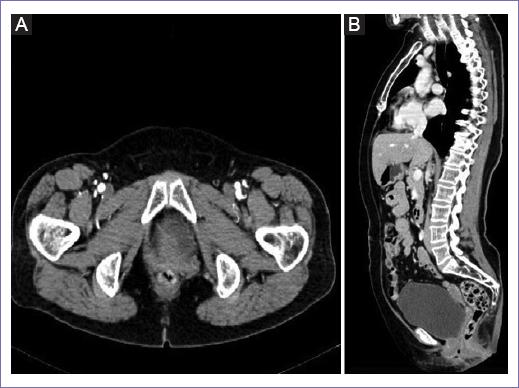

La tomografía computarizada (TC) torácica, abdominal y pélvica no mostró datos de actividad tumoral en región abdominal ni retroperitoneal, solo mostró un quiste simple dependiente del anexo derecho y aumento de reforzamiento en la región del cérvix con extensión al canal vaginal del lado izquierdo (Figs. 1 y 2). Así mismo, se realizó un ultrasonido endovaginal documentando un útero de 46 x 17 mm, endometrio lineal, cérvix sin alteraciones, anexo derecho con imagen anecoica, bien delimitada de 2 x 2 cm avascular y anexo izquierdo sin alteraciones.

Figura 2 A: plano axial de la TC que muestra aumento de densidad en el cuello uterino con una extensión vaginal predominantemente izquierda. B: plano sagital de la TC donde no se observan alteraciones de imagen a nivel de recto y vejiga.